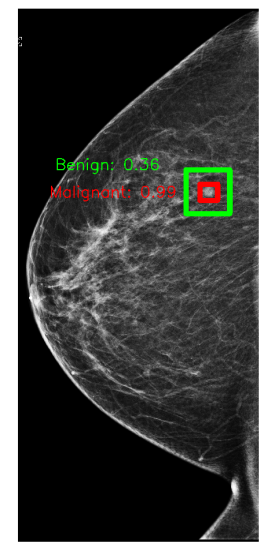

In Figure 1, we show an annotation and the corresponding prediction using an X-101 model. The model accurately predicts a malignant lesion with high probability (0.99). It also predicts a benign lesion with low probability (0.36) for which there is no ground-truth annotation. These bounding boxes can highlight suspicious regions and help radiologists understand predictions from our models.